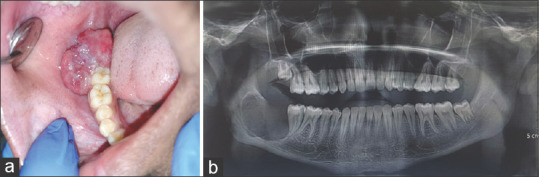

An 18-year-old male presented with a 3-week history of progressively enlarging nodular growth in the posterior right mandibular region. The patient denied the use of tobacco in any form or history of trauma, and his family history was unremarkable. Clinical examination revealed a 2 × 3 cm reddish-pink, firm lesion with palpable submandibular lymph nodes. Radiological imaging showed a well-defined radiolucency distal to tooth #47. An incisional biopsy revealed the proliferation of spindle cells and ameloblastomatous epithelium showing features like pleomorphism, cellular crowding, and mitotic figures. Immunohistochemical analysis confirmed odontogenic origin. Based on the above findings, the diagnosis of the spindle cell variant of ameloblastic carcinoma (AC) was rendered. AC, constituting less than 2% of odontogenic tumours, and the spindle cell variant, a rare subtype with fewer than 15 reported cases, pose diagnostic challenges, necessitating careful histopathological and immunohistochemical evaluation for accurate diagnosis and treatment planning.